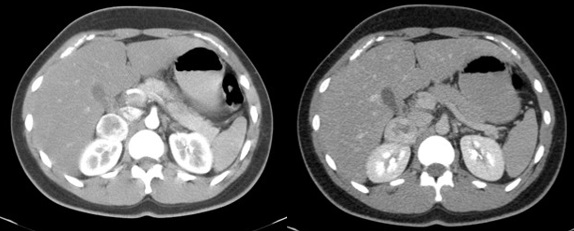

Se presenta el caso de un paciente masculino de 18 años sin antecedentes, que consulta por dolor en hipocondrio derecho de un año de evolución, asociado a palpitaciones, y episodios de HTA. El examen de orina de 24 horas mostró niveles elevados de catecolaminas. En la ecografía abdominopélvica y TAC abdominal, se objetiva una formación de aspecto nodular sólida hipoecoica de contornos bien delimitados, de aproximadamente 43 mm x 39 mm, que no muestra vascularización a la señal Doppler color, asociado a la TC abdomen con contraste EV: masa sólida de 38 mm x 31 mm, reemplazando el parénquima de la glándula suprarrenal derecha que realza de forma ávida y heterogénea en fase arterial a expensas de área central con degeneración necrótica. Se prepara con alfa bloqueador, se realiza adrenalectomía total izquierda laparoscópica. La anatomía patológica evidencia feocromocitoma.

El feocromocitoma es una entidad que afecta a pacientes jóvenes y tiene diversos hallazgos imagenológicos, siendo los más característicos por ecografía como masas grandes sólidas o quísticas con calcificaciones, de bordes bien definidos, dependiente de una glándula suprarrenal, en la TAC suelen ser heterogéneas, frecuente la calcificación, hemorragia y necrosis, con marcado realce tras la administración de contraste. Siendo este el gold standard con el protocolo de lavado suprarrenal se compone de una fase sin contraste, una exploración contrastada con un retraso de 60-90 segundos y una tardía a los 15 minutos con densidad > 10UH.